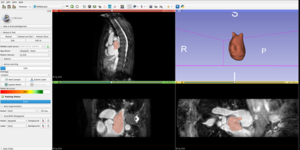

CardIAc: An Open-Source Application for Myocardial Strain Analysis